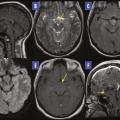

Hamartome hypothalamique

HAMARTOME

Image